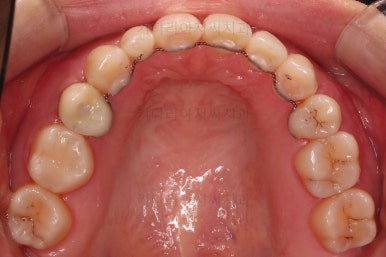

장치 부착 직후의 모습인데요.

장치가 어디있냐고요?

이번 환자분이 선택하신 장치는 인비절라인이라는 투명교정장치였기 때문에 치아에는 유심히 관찰해 보면 보이는 작은 치아색깔의 어태치먼트라는 버튼 이외에는 부착물이 없답니다.

저 상태로 투명교정장치를 빼고 끼면서 치아를 움직이게 됩니다.

필요한 발치, 급한 충치치료는 마무리된 상태이고요.

장치 착용 모습인데요.

교정 중임에도 불구하고 거의 눈에 띄지 않는다는 압도적인 장점이 있죠.